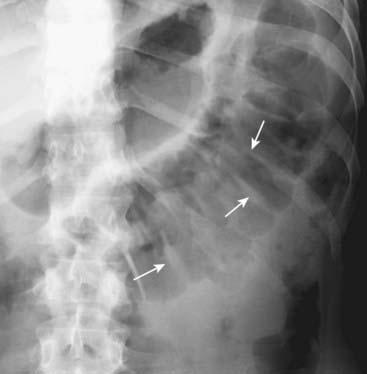

Figure 13-19 Calcified rib cartilages.

Calcification of the rib cartilages (white circle) occurs with advancing age and, while not a true abdominal calcification, can sometimes be confused for calculi when it overlies the kidney or region of the gallbladder. Calcified cartilage tends to have an amorphous, mottled appearance. Calcified rib cartilages will occur along an arc corresponding to the sweep of the anterior ribs as they turn back toward the sternum.